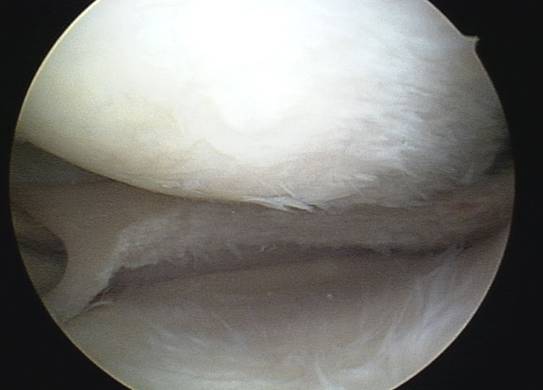

Arthroskopischer Kreuzbandersatz

Wie läuft die Operation ab ?

Eine Kreuzbandersatzplastik ist sehr elektive Operation, die ERST !!! dann durchgeführt werden soll, wenn sich das zu operierte Kniegelenk von dem Unfall " erholt " hat und möglichst abgeschwollen, schmerzfrei beweglich ist. Wird der Eingriff am immer noch deutlich gereizten Knie durchgeführt, ist es mit wesentlich längerer Nachbehandlungszeit, hartnäckigen Restbeschwerden und nicht selten Beweglichkeitseinschränkung

zu rechnen.

Diese arthroskopische Operation kann entweder ambulant oder stationär durchgeführt werden. Wir bieten beide Optionen an.

Man kann zwischen Vollnarkose und Spinalanästhesie wählen. Selbstverständlich werden auch alle anderen Verletzungen im Knie ( Meniskusriss, Knorpelschaden ) gleichzeitig mitbehandelt. Von mehreren Operationen wegen einer Knieverletzung ist intensiv abzuraten, trotzdem sieht man dies immer wieder!

Nach präziser arthroskopischer Anlage von zwei Bohrkanälen jeweils ein im Oberschenkelknochen und Schienbeinkopf, wird das VKB Transplantat aus einer oder zwei körpereigenen Sehnen ( Semitendinosus, Gracilis ) ins Kniegelenk eingezogen und in den Kanälen befestigt.

Die Op Dauer beträgt 30-45 Minuten, ggf. länger bei gleichzeitiger Versorgung von Begleitverletzungen.